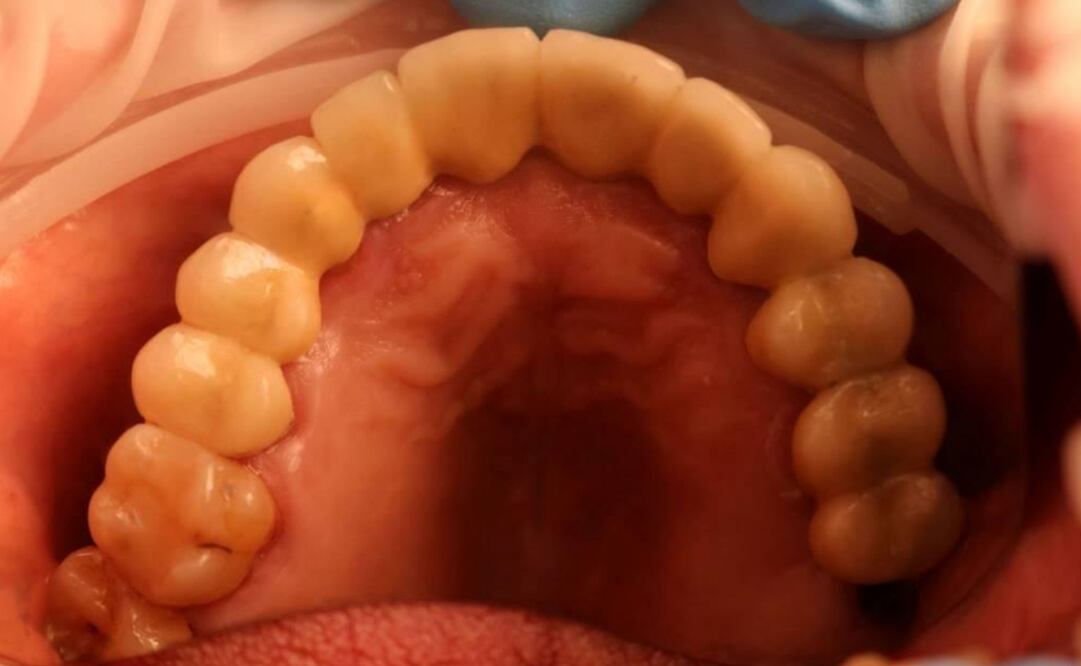

Un equipo internacional de científicos ha descubierto cómo los dientes perciben el frío y han señalado los actores moleculares y celulares implicados. Tanto en los ratones como en los humanos, las células dentales llamadas odontoblastos contienen proteínas sensibles al frío que detectan los descensos de temperatura, informan en la revista Science Advances . Las señales de estas células pueden desencadenar una sacudida de dolor en el cerebro.

Los dientes se deterioran cuando las películas de bacterias y el ácido corroen el esmalte, la cubierta dura y blanquecina de los dientes. A medida que el esmalte se erosiona, se forman unas fosas llamadas caries. Alrededor de 2 mil 400 millones de personas --un tercio de la población mundial-- tienen caries sin tratar en los dientes permanentes, lo que puede provocar un intenso dolor, incluida una extrema sensibilidad al frío .

El TRPC5 reside en los dientes, y más aún en los que tienen caries, según descubrió Jochen Lennerz, coautor del estudio y patólogo del Hospital General de Massachusetts, tras examinar muestras de adultos humanos.

El TRPC5 reside en los dientes, y más aún en los dientes con caries, según descubrió el coautor del estudio Jochen Lennerz, patólogo del Hospital General de Massachusetts , tras examinar muestras de adultos humanos.

El equipo localizó la ubicación de TRPC5 en un tipo de célula específica, el odontoblasto, que reside entre la pulpa y la dentina. Cuando alguien con un diente expuesto a la dentina muerde una paleta, por ejemplo, esas células repletas de TRPC5 captan la sensación de frío y una señal de "¡ay!" llega al cerebro.